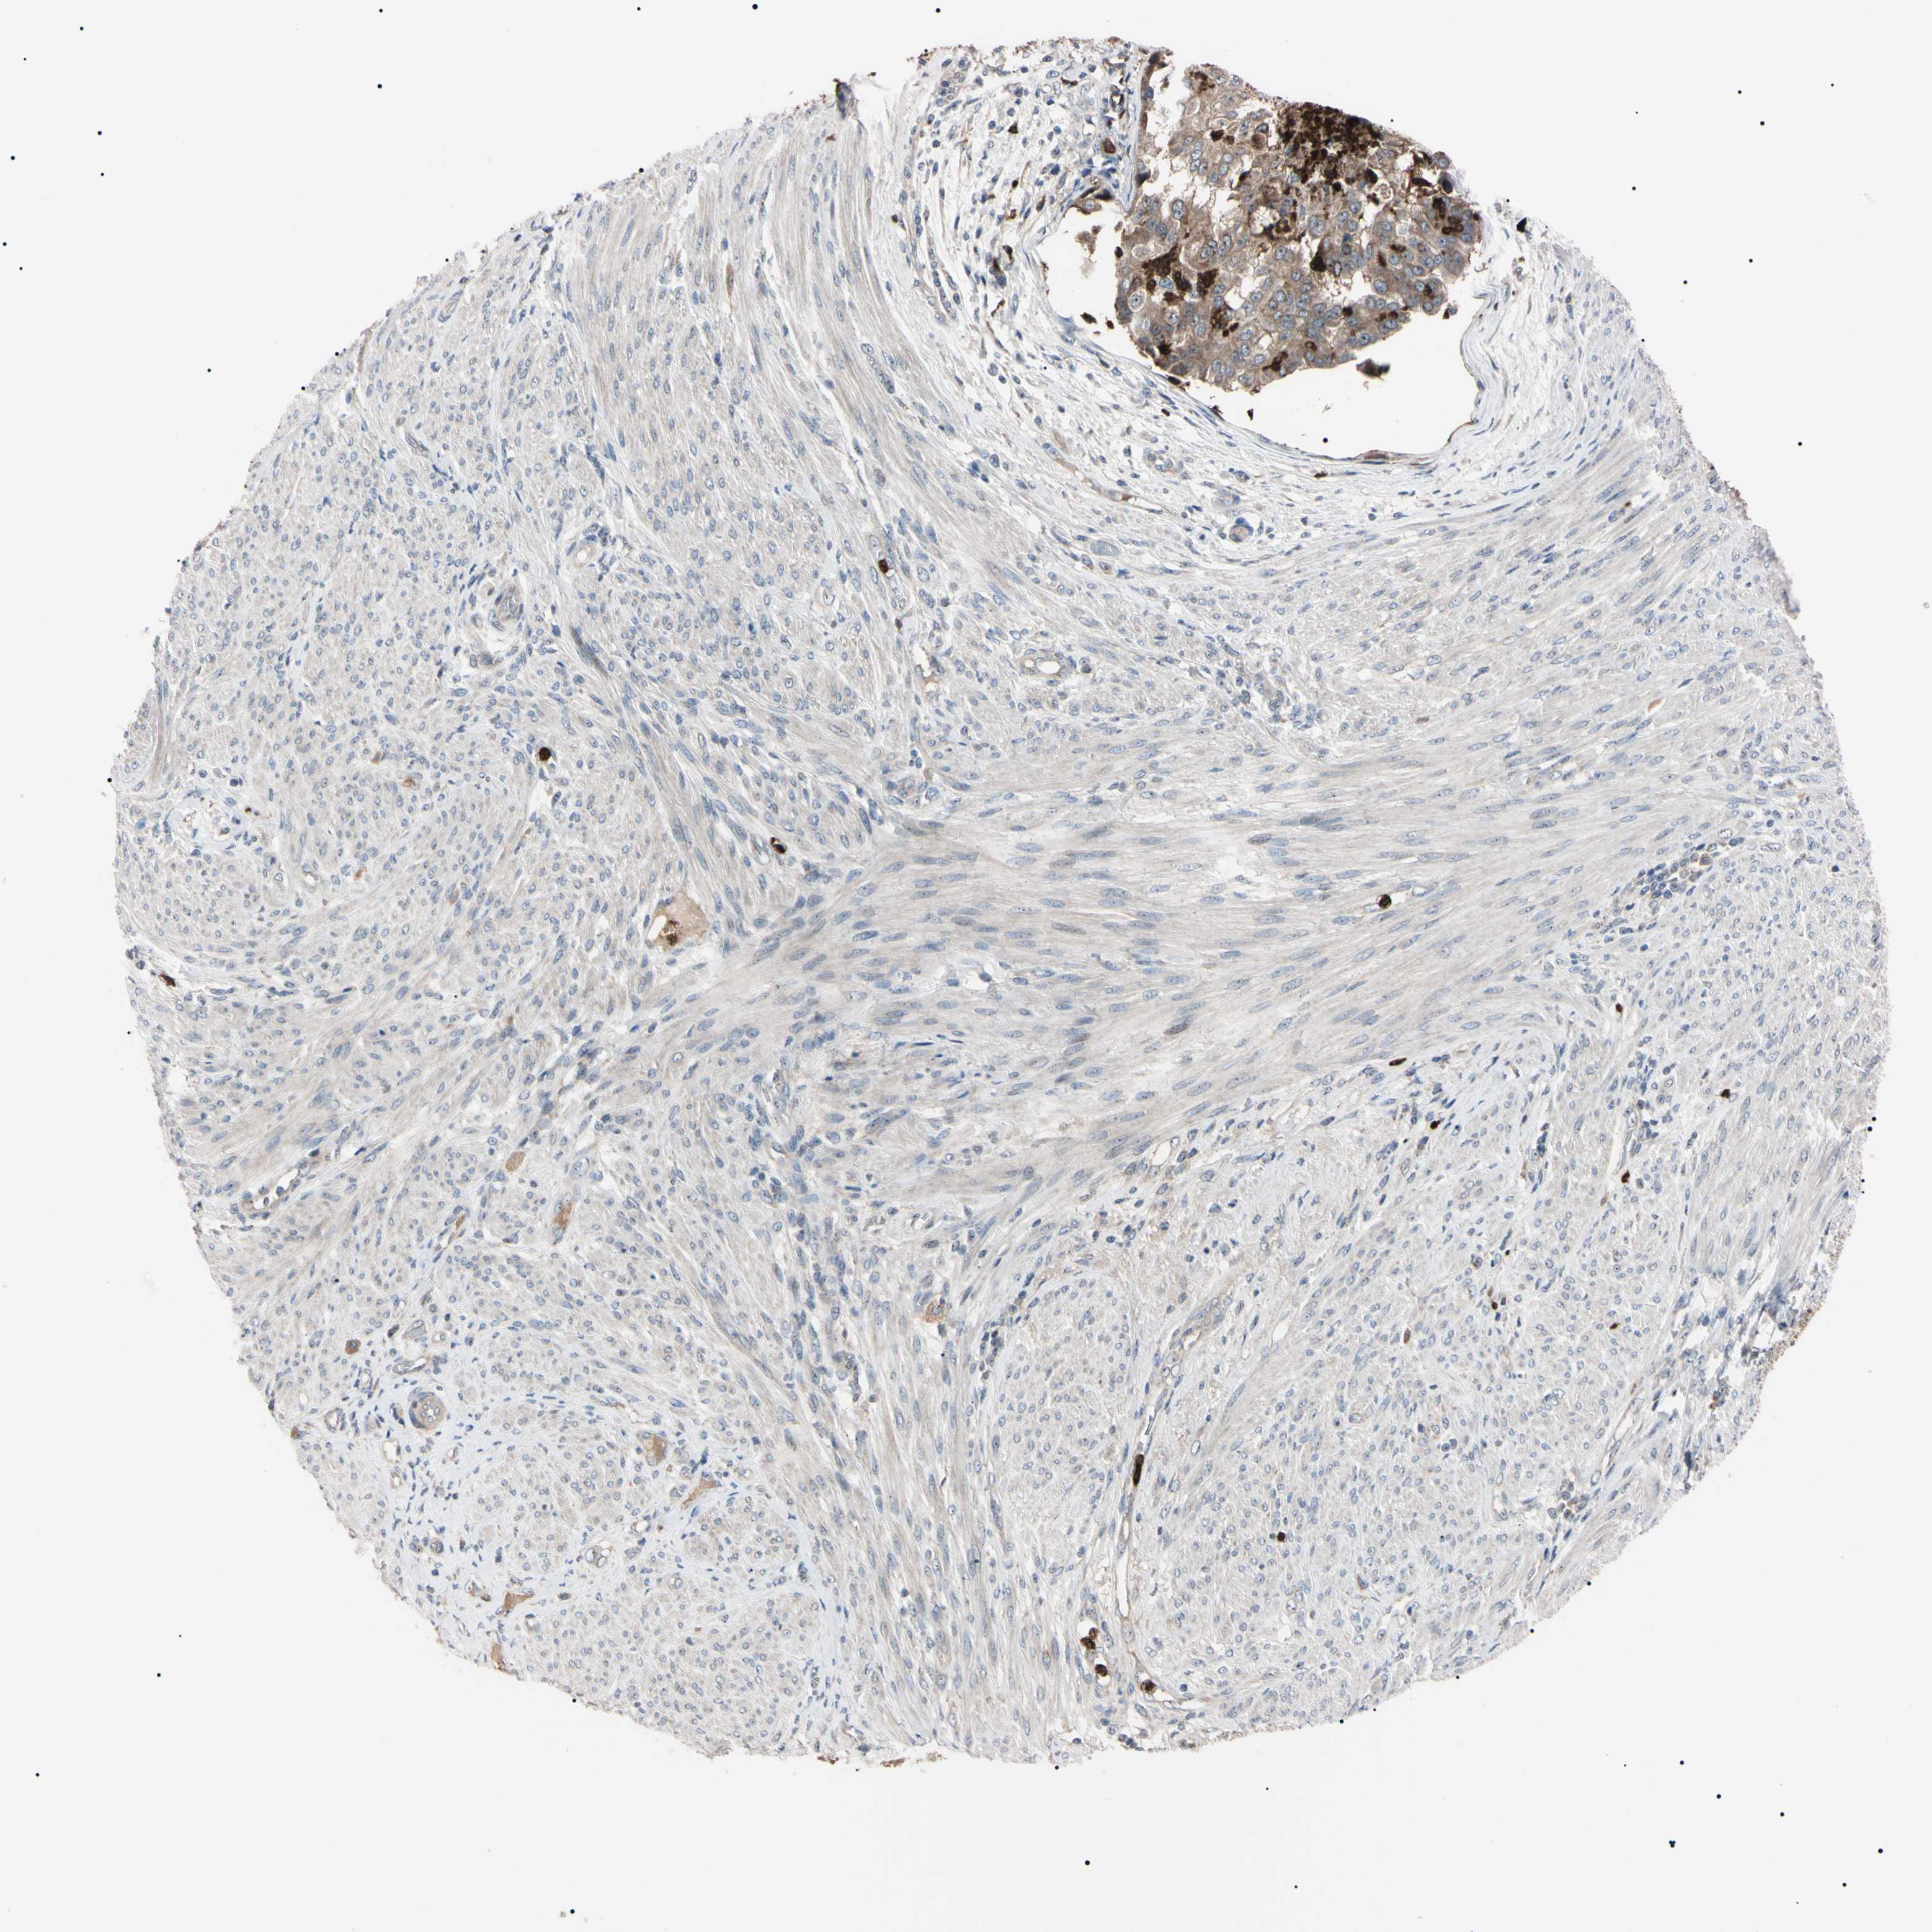

ENDOMETRIAL CANCER - Protein expressioni

A mouse-over function shows sample information and annotation data. Click on an image to view it in a full screen mode. Samples can be filtered based on level of antibody staining by selecting one or several of the following categories: high, medium, low and not detected. The assay and annotation is described here.

Note that samples used for immunohistochemistry by the Human Protein Atlas do not correspond to samples in the TCGA dataset.

Antibody stainingi

Antibody staining in the annotated cell types in the current human tissue is reported as not detected, low, medium, or high, based on conventional immunohistochemistry profiling in selected tissues. This score is based on the combination of the staining intensity and fraction of stained cells.

Each image is clickable and will lead to virtual microscopy that enables deeper exploration of all samples and also displays staining intensity scores, fraction scores and subcellular localization as well as patient and tissue information for each sample.

Antibody HPA008052

Antibody CAB010277

Staining

High

Medium

Low

Not detected

Intensity

Strong

Moderate

Weak

Negative

Quantity

>75%

75%-25%

<25%

None

Location

Nuclear

Cytoplasmic/membranous

Cytoplasmic/membranous,nuclear

Adenocarcinoma, NOS